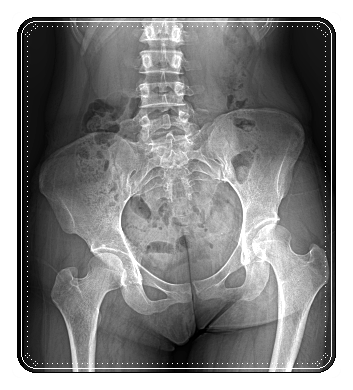

조금 더 설명하자면, 수술 과정에서 골반 주변의 근육과 관절, 신경, 그리고 순환 구조가 영향을 받게 됩니다.

“특히 골반은 몸의 중심입니다.”

골반이 조금만 틀어져도 걷는 방식이나 앉는 자세, 허리의 움직임까지 달라지게 되는데요.

이러한 변화가 쌓이게 되면 수술후 골반통증이 생각보다 오래 지속될 수 있습니다.